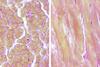

What is pictured

mucous glands on the left and serous glands on the right